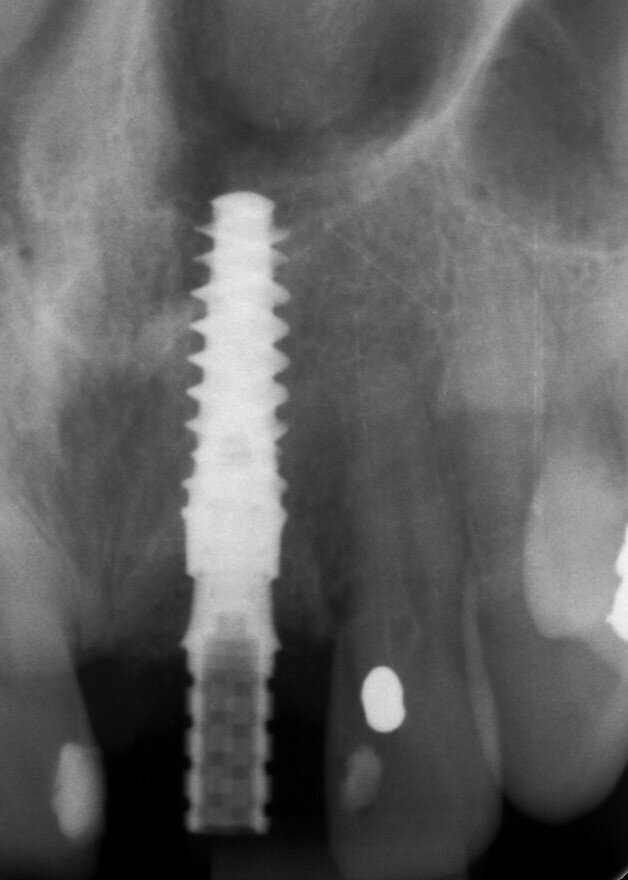

Una paziente di 53 anni si è presentata in studio con un incisivo sinistro fratturato a cui era stata più volte cementata una corona di ceramica (Figg. 1, 2). L’anamnesi e gli esami hanno evidenziato una buona salute sistemica e orale, un’occlusione ben equilibrata e nessuna abitudine al fumo. La tomografia cone beam (CBCT) e la radiografia periapicale hanno mostrato un riassorbimento radicolare esterno con inserimento nell’osso alveolare molto scarso, insufficiente per un adeguato posizionamento di un comune perno endocanalare (Figg. 3, 4). Considerando che il dente fratturato si trovava nella zona estetica, il paziente richiese un restauro nel modo più sicuro e più veloce possibile.

Fig. 3_Radiografia periapicale pre-operatoria.

Fig. 4_Scansione CBCT pre-operatoria.